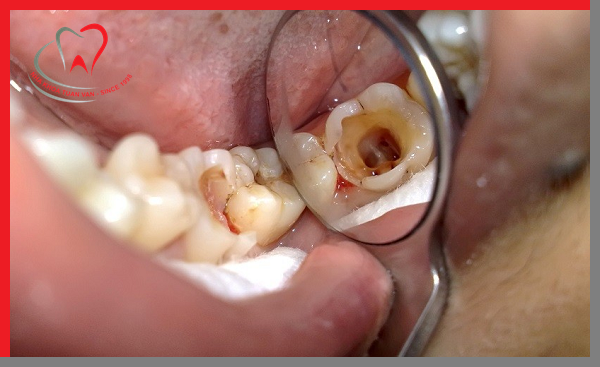

1. Lấy tuỷ răng xong bị đau: Theo đúng bình thường, sau khi lấy tủy răng xong thì răng sẽ không còn cảm giác đau nhức hay là cảm nhận được nhiệt nữa. Tuy nhiên, do một số nguyên nhân dưới đây mà sau khi lấy tủy răng xong bị đau:

- Quá trình lấy tủy răng chưa triệt để, phần tủy bị viêm vẫn còn sót lại ở trong răng, vì vậy mà bệnh viêm tủy răng vẫn phát triển dù đã lấy tủy rồi.

- Tay nghề của bác sĩ chưa cao, khi lấy tủy không cẩn thận gây thủng sàn tủy hoặc chóp tủy.

- Thao tác trám bít ống tủy không cẩn thận, không tạo được sự đầy đặn và sát khít.